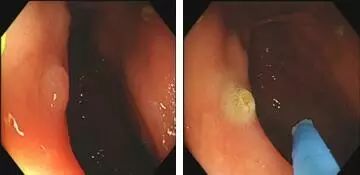

热活检钳电凝钳除术:

为什么说热活检钳胃肠息肉是怎么长出来的?有什么危害?如何预防和治疗?_https://www.jmylbn.com_新闻资讯_第13张1.发现息肉;2.热活检钳夹住息肉;3.钳除息肉